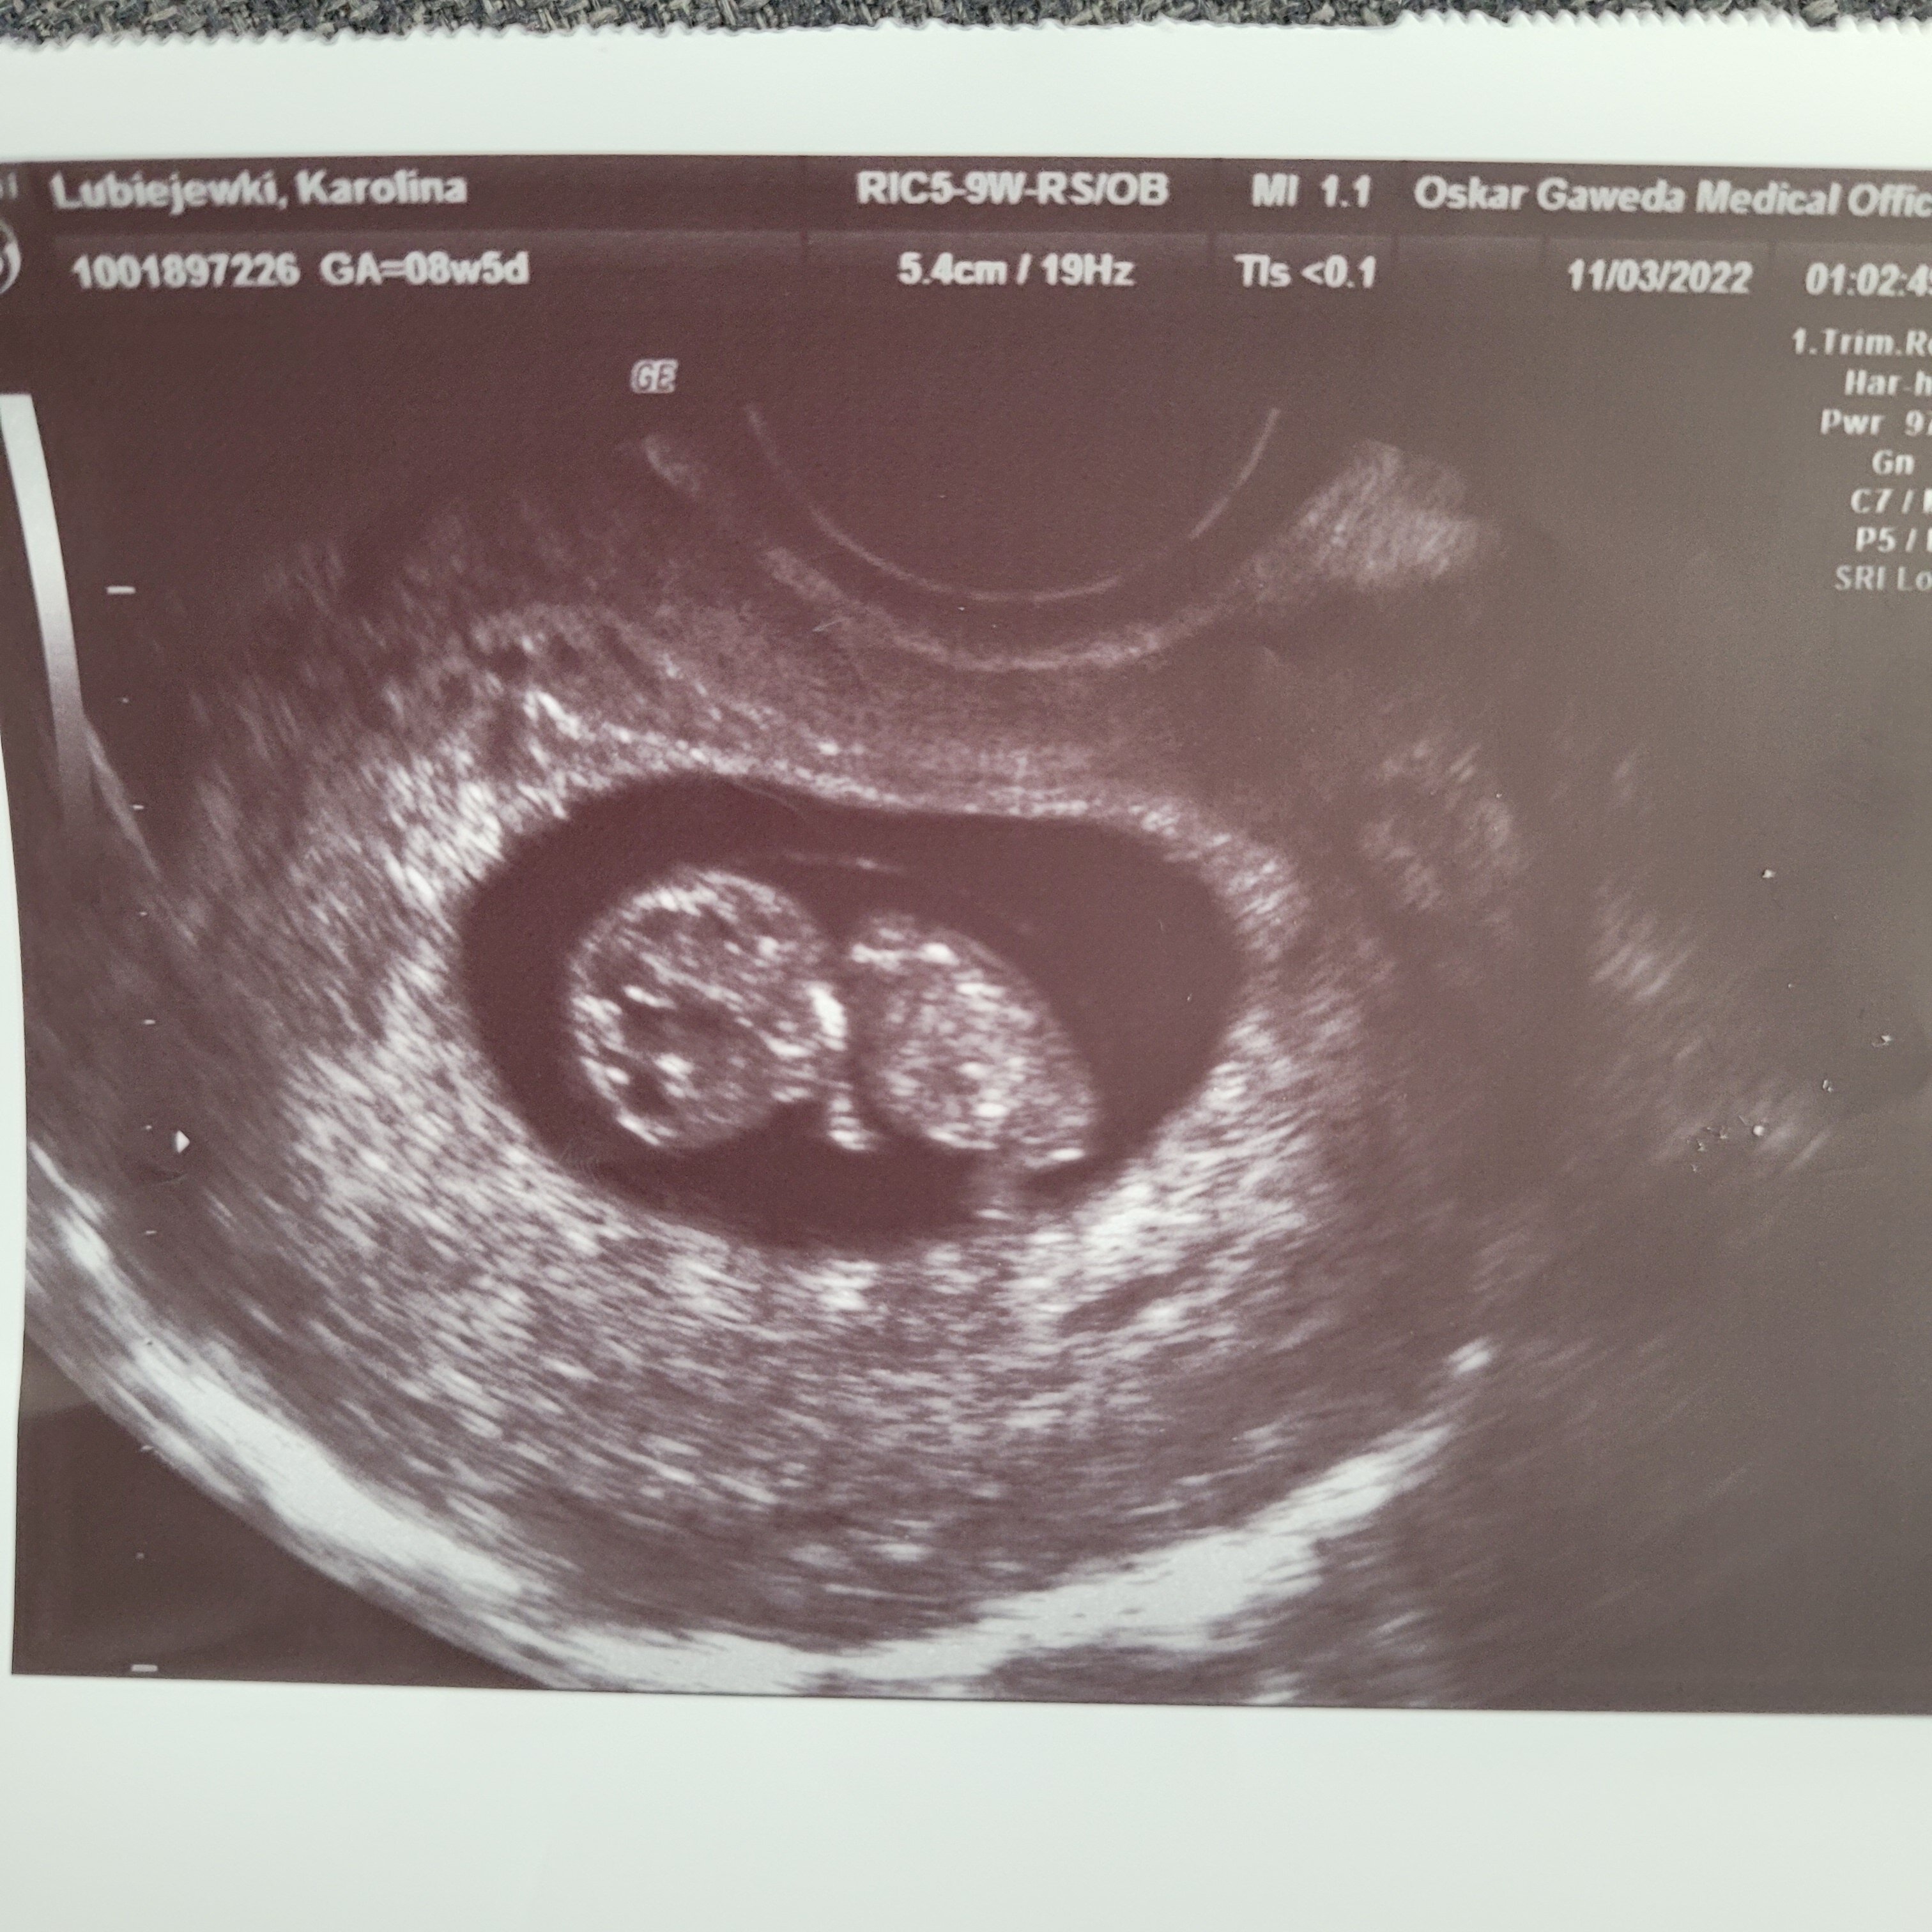

Pięknie już wszystko widać jak na ten termin z omBaby ma sie dobrze,serduszko pieknie bije 170 na minuteUspokoilam sie